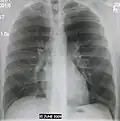

| A chest X-ray showing a very prominent wedge-shape bacterial pneumonia in the right lung | |

The discovery of x-rays made it possible to determine the anatomic type of pneumonia without direct examination of the lungs at autopsy and led to the development of a radiological classification. Early investigators distinguished between typical lobar pneumonia and atypical (e.g. Chlamydophila) or viral pneumonia using the location, distribution, and appearance of the opacities they saw on chest x-rays. Certain x-ray findings can be used to help predict the course of illness, although it is not possible to clearly determine the microbiologic cause of a pneumonia with x-rays alone.